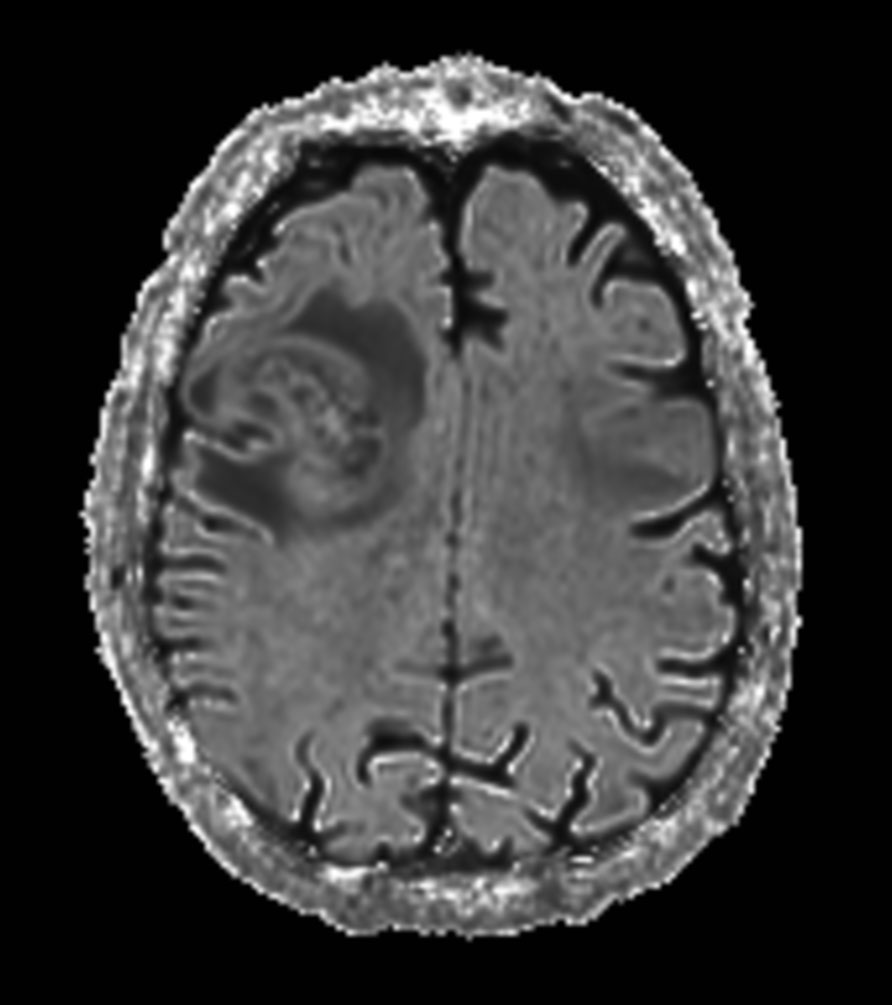

Axial SWIp

-

Axial SWIp (Min IP)